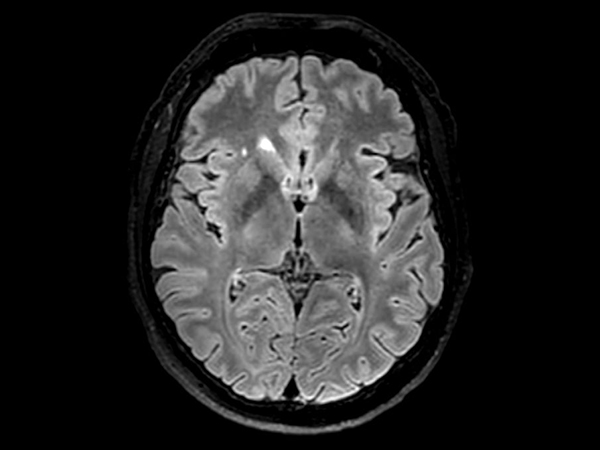

3D VIEW - T2w FLAIR (axial reformat)

3D VIEW - T2w TSE (axial reformat)